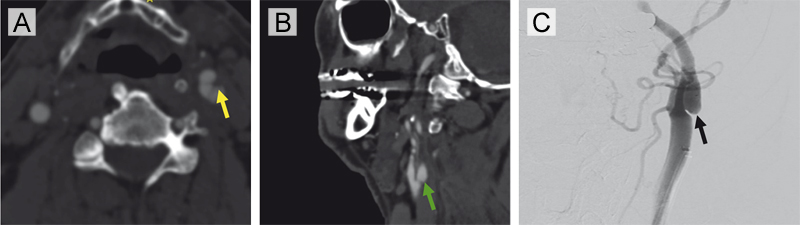

Figure 5. Radiographic imaging of a carotid artery web (CW) without evidence of superimposed thrombus in a patient with recurrent large-vessel occlusions (Case 3).

(A) Axial CTA demonstrates a shelf-like projection along the posterior wall of the left internal carotid artery, consistent with a carotid web in the proximal left ICA (yellow arrow). (B) Corresponding sagittal CTA confirms the non-stenotic web morphology in the absence of atherosclerosis (green arrow). (C) Digital subtraction angiography (left common carotid contrast injection) reveals a subtle web-like filling defect in the proximal consistent with a carotid artery web (black arrow).